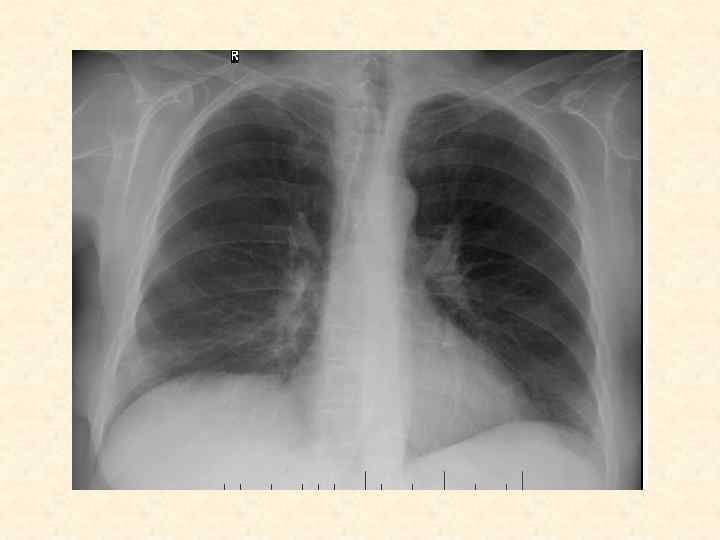

Пневмонии Томск, 2014 -2015 уч. год

Пневмония – это острый воспалительный процесс в респираторной зоне легких инфекционной природы, возникающий самостоятельно, или вторично – как осложнение другого заболевания

Формирование диагностической гипотезы о пневмонии • • • Синдромы: Уплотнение легких Общая воспалительная реакция Болевой синдром Бронхитический синдром Психотические изменения ………. .

Определение основного синдрома Синдром, отражающий анатомическую локализацию воспаления: - Уплотнение легких Связь между уплотнением легких и общей воспалительной реакцией доказывает: - Болевой - Бронхитический (боли и извержения из легких)